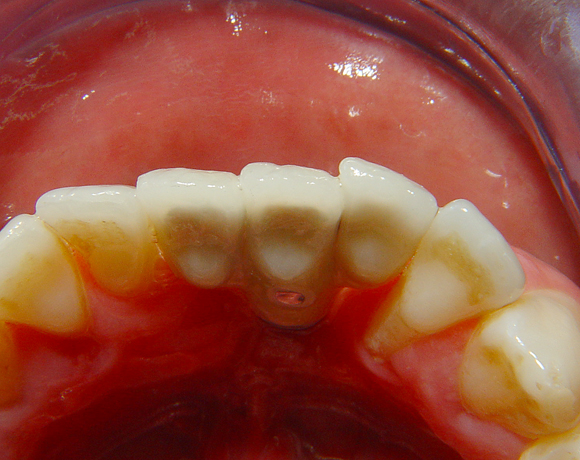

Diese Frontzahnsituation stellte den Behandler vor größere Probleme

Durch Abrasion der Seitenzähne wurden die Frontzähne nach labial verdrängt und lückig. Nach Verlust des Zahnes 41 entstand eine Lücke in der drei Zähne Platz fanden. Auch im Oberkiefer wurden die lateralen Lücken mit Veneers verkleinert.